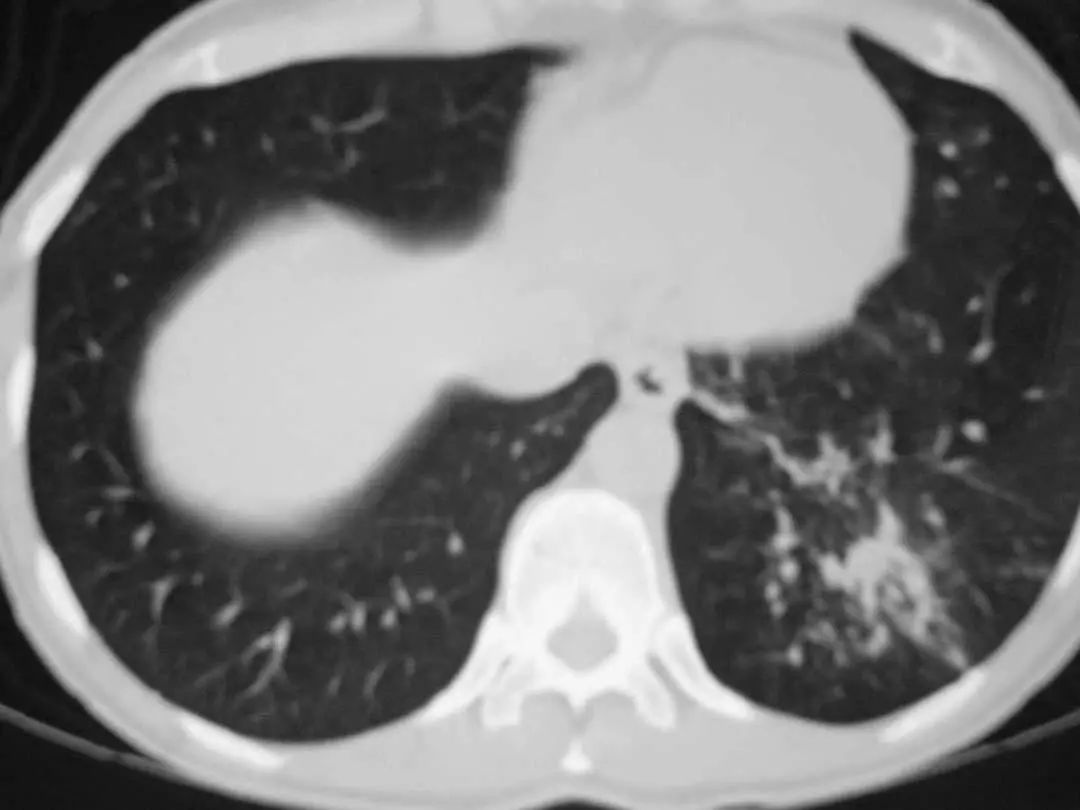

图1.2 细菌性肺炎。双肺下叶肺炎患者影像。

图1.3 细菌性肺炎。早期右肺中叶肺炎的影像学表现。